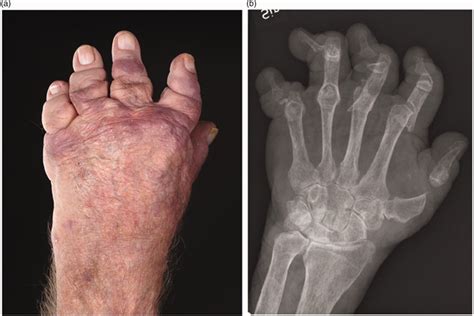

Cualquier forma de psoriasis puede acompañar a la artritis. La AP es una enfermedad inflamatoria articular y extraarticular. La mayoría de pacientes presenta mono, oligo o poliartritis de grandes o pequeñas articulaciones. Normalmente es una enfermedad asimétrica, a diferencia de la AR, y se distingue por la afectación de las articulaciones IFD. Menos del 5% de los pacientes presentan una forma grave, la artritis mutilante.

- Artritis destructiva o mutilante.